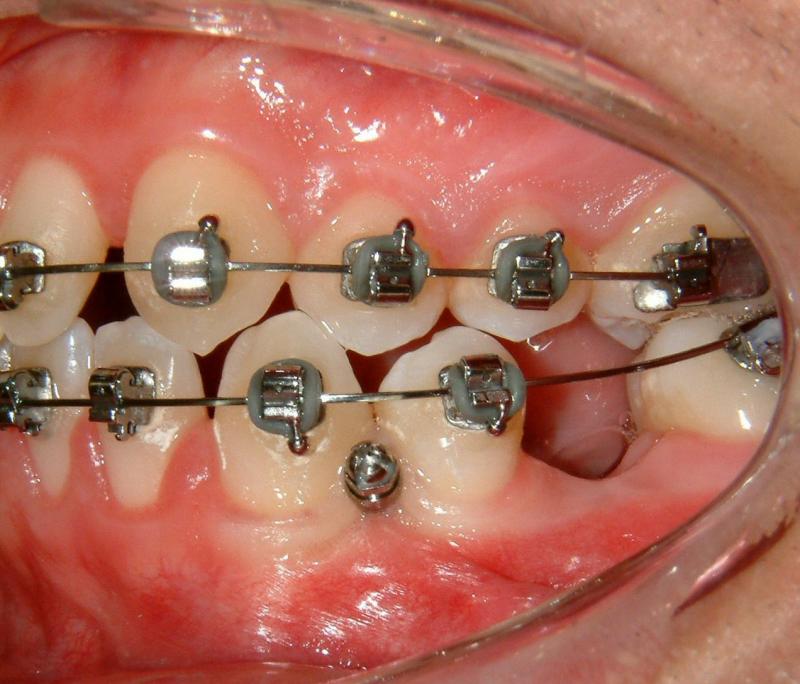

Fig. 4. A TAD (Tomas, Dentaurum) after placement

© Copyright 2007-2014, Vu Orthodontics. All rights reserved.

Fig. 6. Immediate loading for TAD (activated)

It can be seen that Figure 6 shows immediate loading with light activation which is necessary for bone modeling.